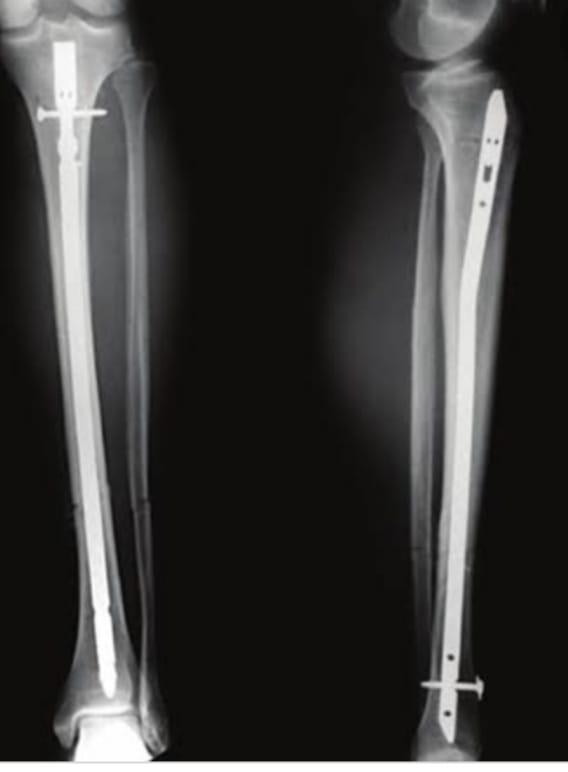

The Veer Hospital provides effective and high-quality healthcare services with 20+ departments, 16 special units and 50+ physicians. We offer an up-to-date medical approach in an ethical and reliable environment. We maintain our reputation in the health sector with our experienced medical staff who continuously improve qualified healthcare with an uncompromising focus when it comes to proficiency and academic values.